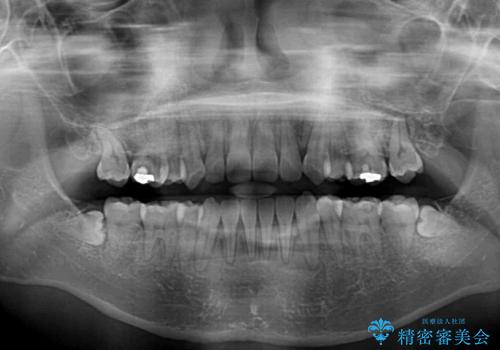

奥歯の咬み合わせが理想的であり、歯の移動に時間のかかる出っ歯でもなかったため、2年程度で治療を終えることを目標としましたが、無事に予定通りの2年間で終えることができました。